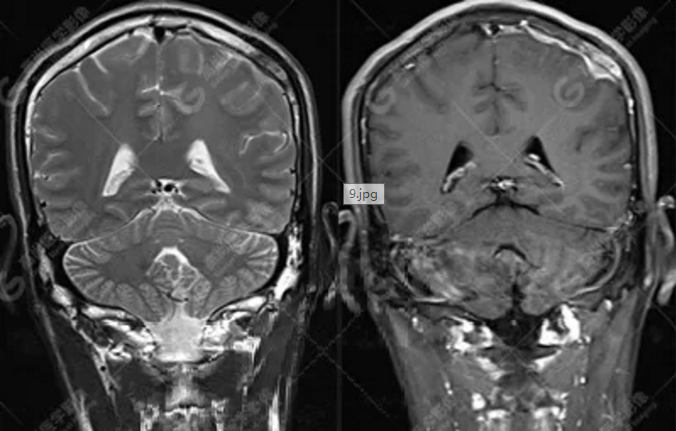

MR圖像

左側額頂部顱骨骨質破壞并相鄰硬腦膜增厚強化,考慮Rosai Dorfman?。≧DD)可能,需與朗格漢斯細胞組織細胞增生癥鑒別。

總之,顱內RDD是一種罕見的硬腦膜良性病變,若 MRI發(fā)現(xiàn)顱內基于硬腦膜扁平或匍匐生長的孤立或者多發(fā)腫塊,CT 檢查未見鈣化,而MR檢查T2WI及 DWI呈低信號,增強明顯均勻強化,應考慮到 RDD 的可能。